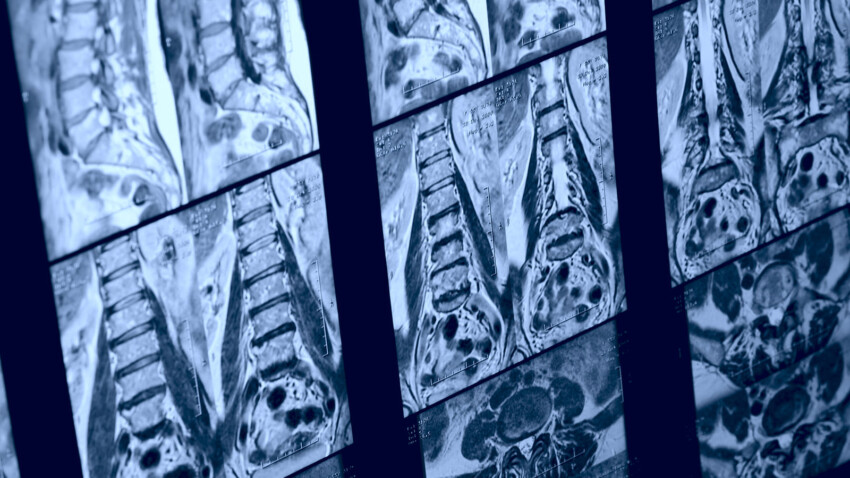

E’ stato ampiamente dimostrato dalla letteratura scientifica come molte delle “anomalie” riscontrabili alla risonanza magnetica facciano parte del normale processo di invecchiamento piuttosto che da traumi accidentali o ripetuti, un po’ come avere i capelli bianchi e le rughe, e non sono sempre associati al dolore.

Molte patologie comuni della colonna vertebrale come ernie discali, degenerazioni discali, protrusioni, ecc…hanno un’alta prevalenza tra individui asintomatici (persone che non hanno mai avuto dolore)

Dalla tabella è possibile notare come il 50% dei giovani di età compresa tra i 30/39 anni, senza nessuna storia di dolore, presenti degenerazione discale, ridotta altezza del disco e bulging discale.

La risposta è NO, la RMN è uno strumento affidabile ma dovrebbe essere sempre contestualizzata nel setting terapeutico in riferimento alle condizioni cliniche del paziente.